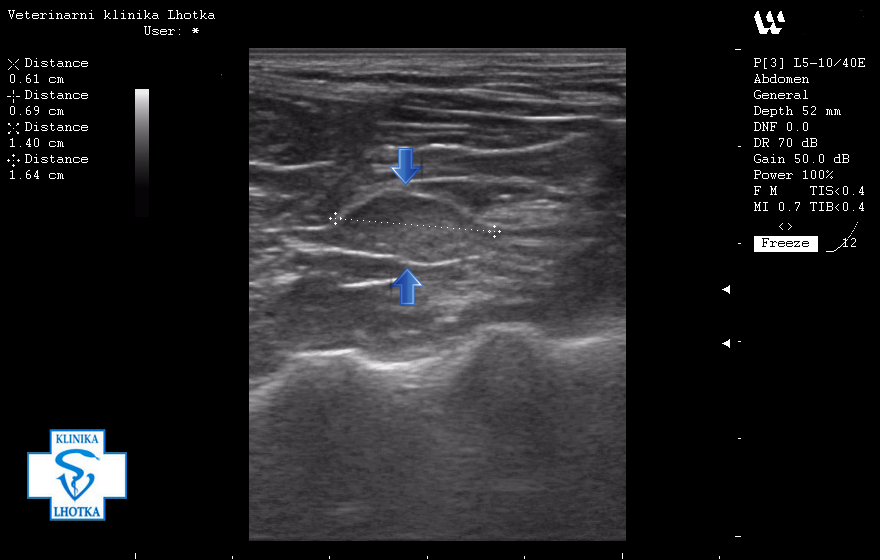

Na ultrazvukových snímcích jsou šipkami označeny metastázy v oblasti jater, levé ledviny, pravděpodobně i v močovém měchýři a v mízních uzlinách pod bederní páteří.

Zde je šipkami ohraničená oblast, kde přechází normální struktura jater v metastázi.

SONO jater - metastáza nádoru mléčné žlázy2